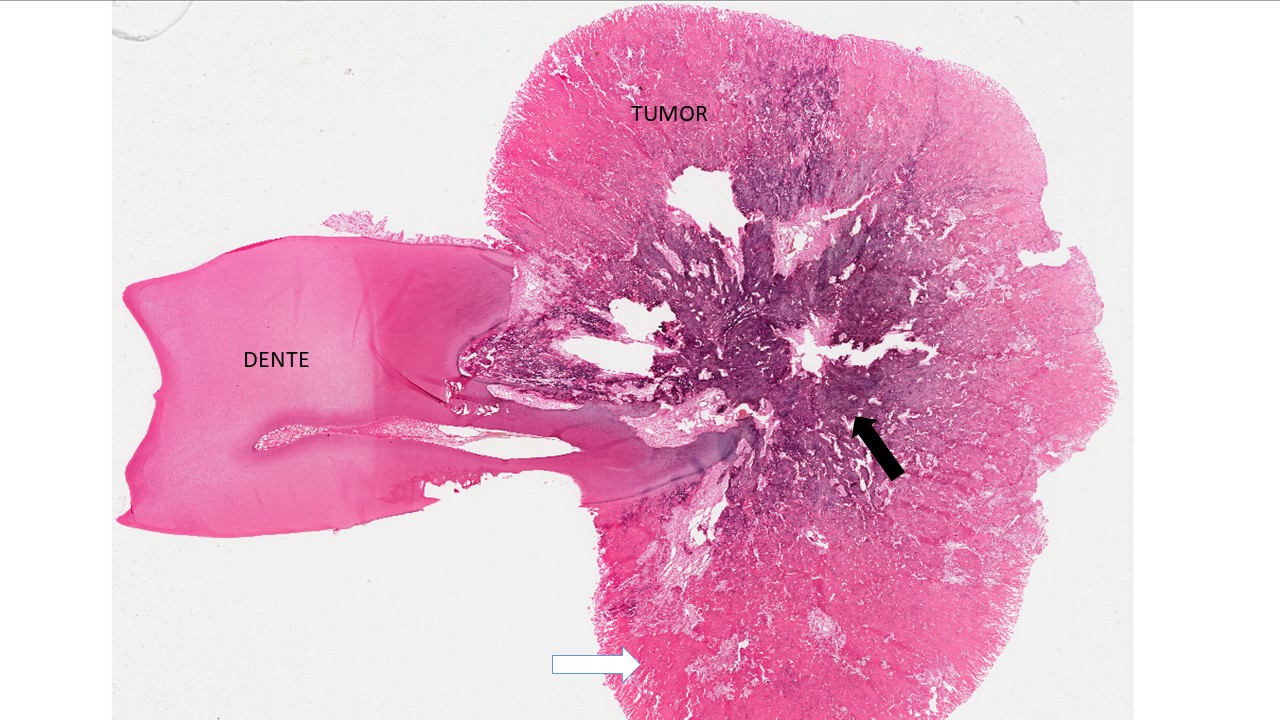

é um tumor benigno intimamente associado às raízes dos dentes. Caracterizado formação exagerada de cemento depositada diretamente em uma raiz dentária.

Descrição microscópica:

microscopicamente o cementoblastoma mostra a formação de tecido mineralizado fusionado ao dente. Esse tecido mineralizado apresenta-se como lençóis e trabéculas de material mineralizado com lacunas posicionadas de forma irregular e linhas reversas basofilicas proeminentes. O estroma é composto de tecido fibrovascular celularizado. Na periferia da lesão encontramos matriz menos calcificada e o centro da lesão matriz mais calcificada.

Dados importantes para diagnóstico:

- Tecido mineralizado fusionado ao dente;

- Matriz menos mineralizado na periferia (seta branca);

- Estroma de tecido conjuntivo fibroso celularizado (asteriscos);

- Centro da lesão com matriz mais mineralizada (setas pretas);